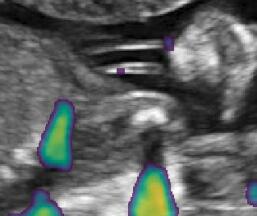

Fig. 6 compares the shadow confidence maps of the state-of-the-art methods and the proposed methods. RW and have the same parameters as used for Table I. The shadow confidence maps of the baseline, the proposed method and the proposedAG method are generated directly from input shadow images by confidence estimation networks. Overall, the proposed method and the proposedAG method achieve more visually reasonable shadow confidence estimation than the baseline and the state-of-the-art on different anatomical structures shown in Fig. 6. The proposed method and the proposedAG method are able to highlight multiple shadow regions while the RW algorithm shows limitations for most cases, especially for disjoint shadow regions.

Row I in Fig. 6 shows a fetal brain image from . The confidence estimation of shadow regions from the baseline, the proposed method and the proposedAG method are similarly accurate since we use fetal brain images to train the confidence estimation networks in these three methods. These outperform [16] and [22]. Rows (II-IV) in Fig. 6 show shadow confidence maps of non-brain anatomy from , including lips, abdominal and cardiac. The baseline failed on unseen data during inference. However, the proposed methods are able to generate accurate shadow confidence maps because of the generalized shadow features obtained by the shadow-seg module. Furthermore, the “Lips” example shows that our method is capable of detecting weaker shadow regions that have not been annotated in manual segmentation. This indicates that the confidence estimation network has learned general properties of shadow regions.